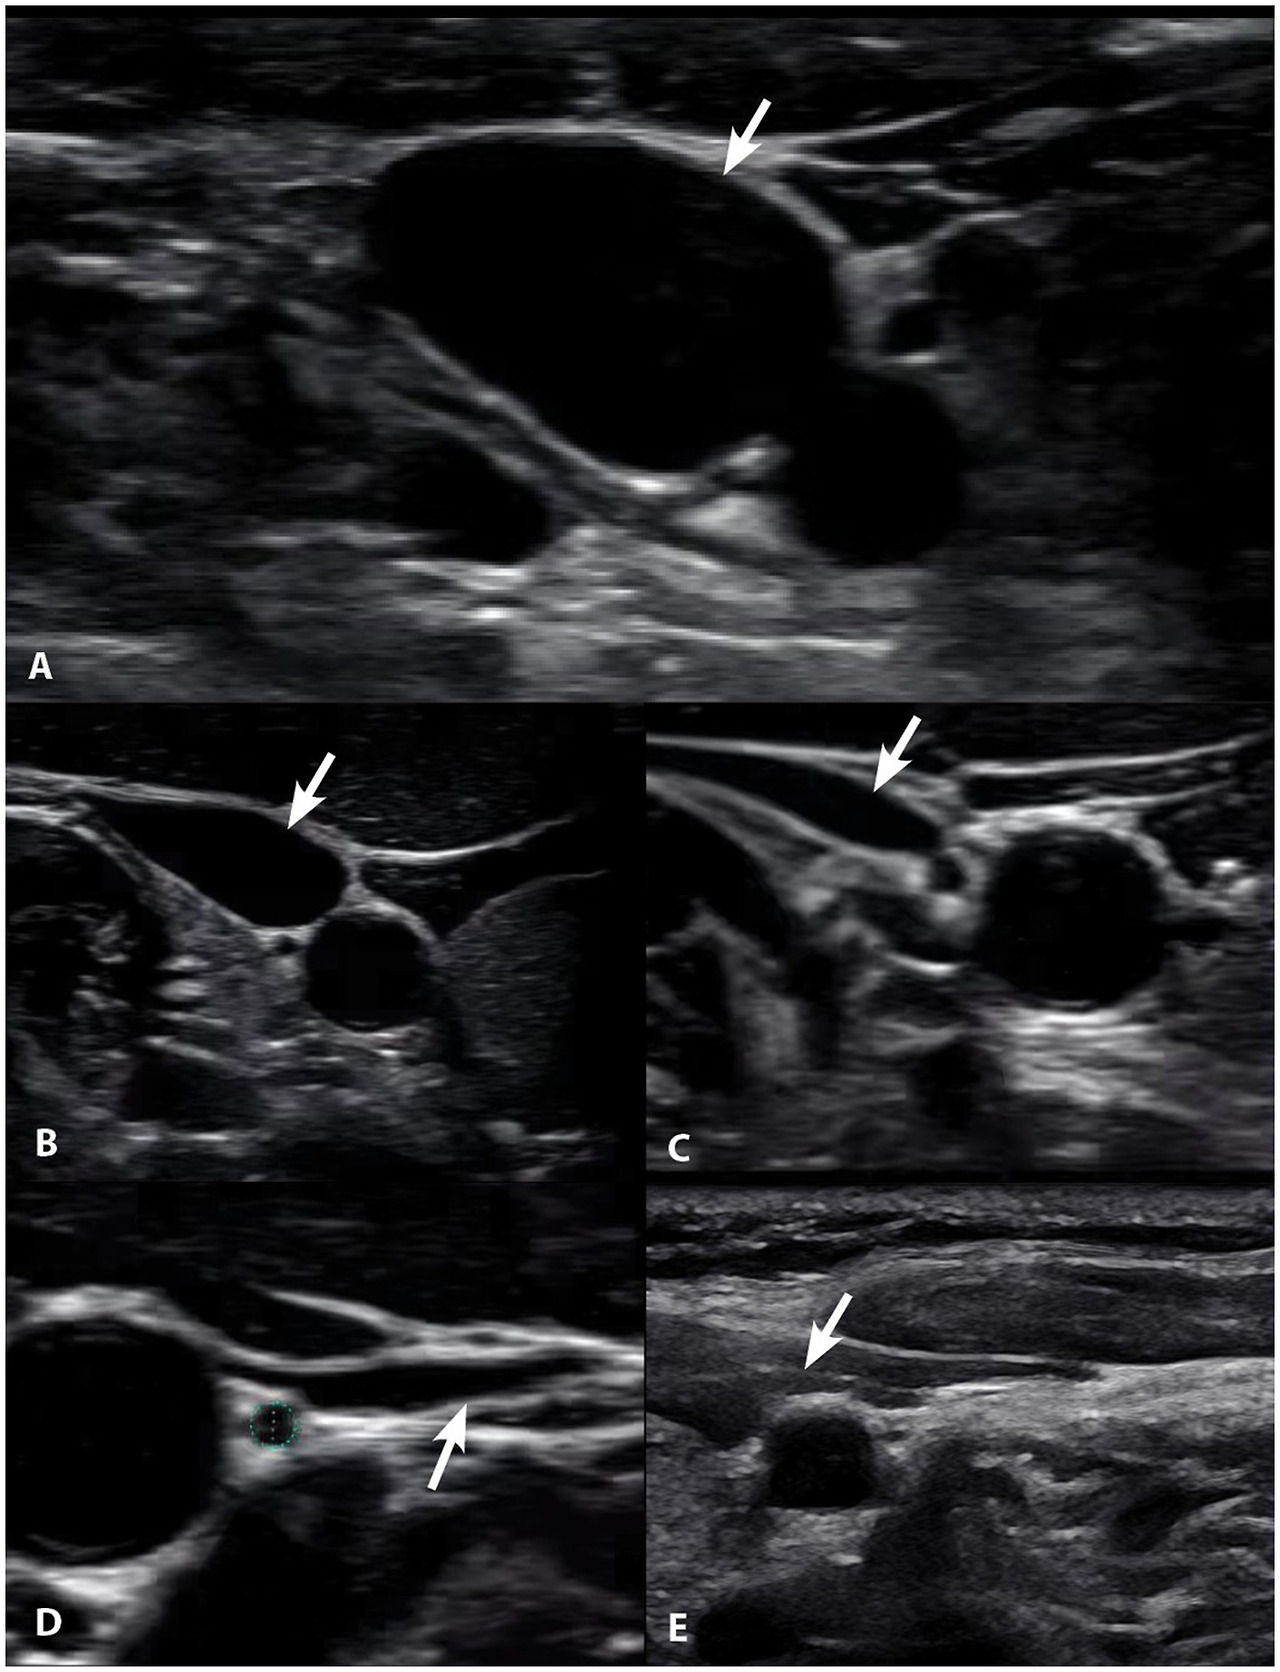

Compression of the carotid sheath, which contains the IJV, can be caused by a narrowing of the space between the lateral mass of C1 and the styloid (3.7 mm of narrowing, in one study) known as the atlantostyloid interval (145). The diameter of the IJV correlating with reduced size of the atlantostyloid interval and the asymmetric larger area of the lateral mass of the atlas on the side of compression (by 40%) suggests LUCI as a reason for the bony size discrepancy (146). Since the styloid is anterior to the carotid sheath, retraction of the head should increase symptoms if an enlarged styloid is the cause of IJV compression; protraction of the head/jaw therefore relieves symptoms, as the atlantostyloid interval increases with that motion. While the gold standard to diagnose IJV compression has been CT venograms, in many cases it is possible for CT or MR venograms done in the supine neck neutral position to miss the IJV compression, as the atlantostyloid interval is narrowed maximally by contralateral head rotation (132). Static neutral scans do not consider compression of the carotid sheath with rotation, flexion, or extension of the neck. Ultrasound eval‎uation while moving the head in different positions can show the narrowing of the IJV at the site of compression (see Figure 10).

Figure 10

Figure 10. Degrees of internal jugular vein compression as seen on ultrasound examination of the neck. (A) Normal, “open” internal jugular vein. (B) Slightly compressed. (C) Moderately compressed. (D) Severely compressed. (E) Completely closed. It is internal jugular vein compression (arrows), especially with upright posture and neck motions, that leads to intracranial hypertension (increased brain pressure).

A proposed cervical ligament etiology of IBP is the 3:1 to 18:1 female preponderance, often relieved by lying down, and the fact that neck flexion and rotation can increase ICP by almost 9 mmHg (147149). In fact, 90% of the patients are females of childbearing age (the most flexible adults), again possibly pointing to cervical instability as a cause (150).